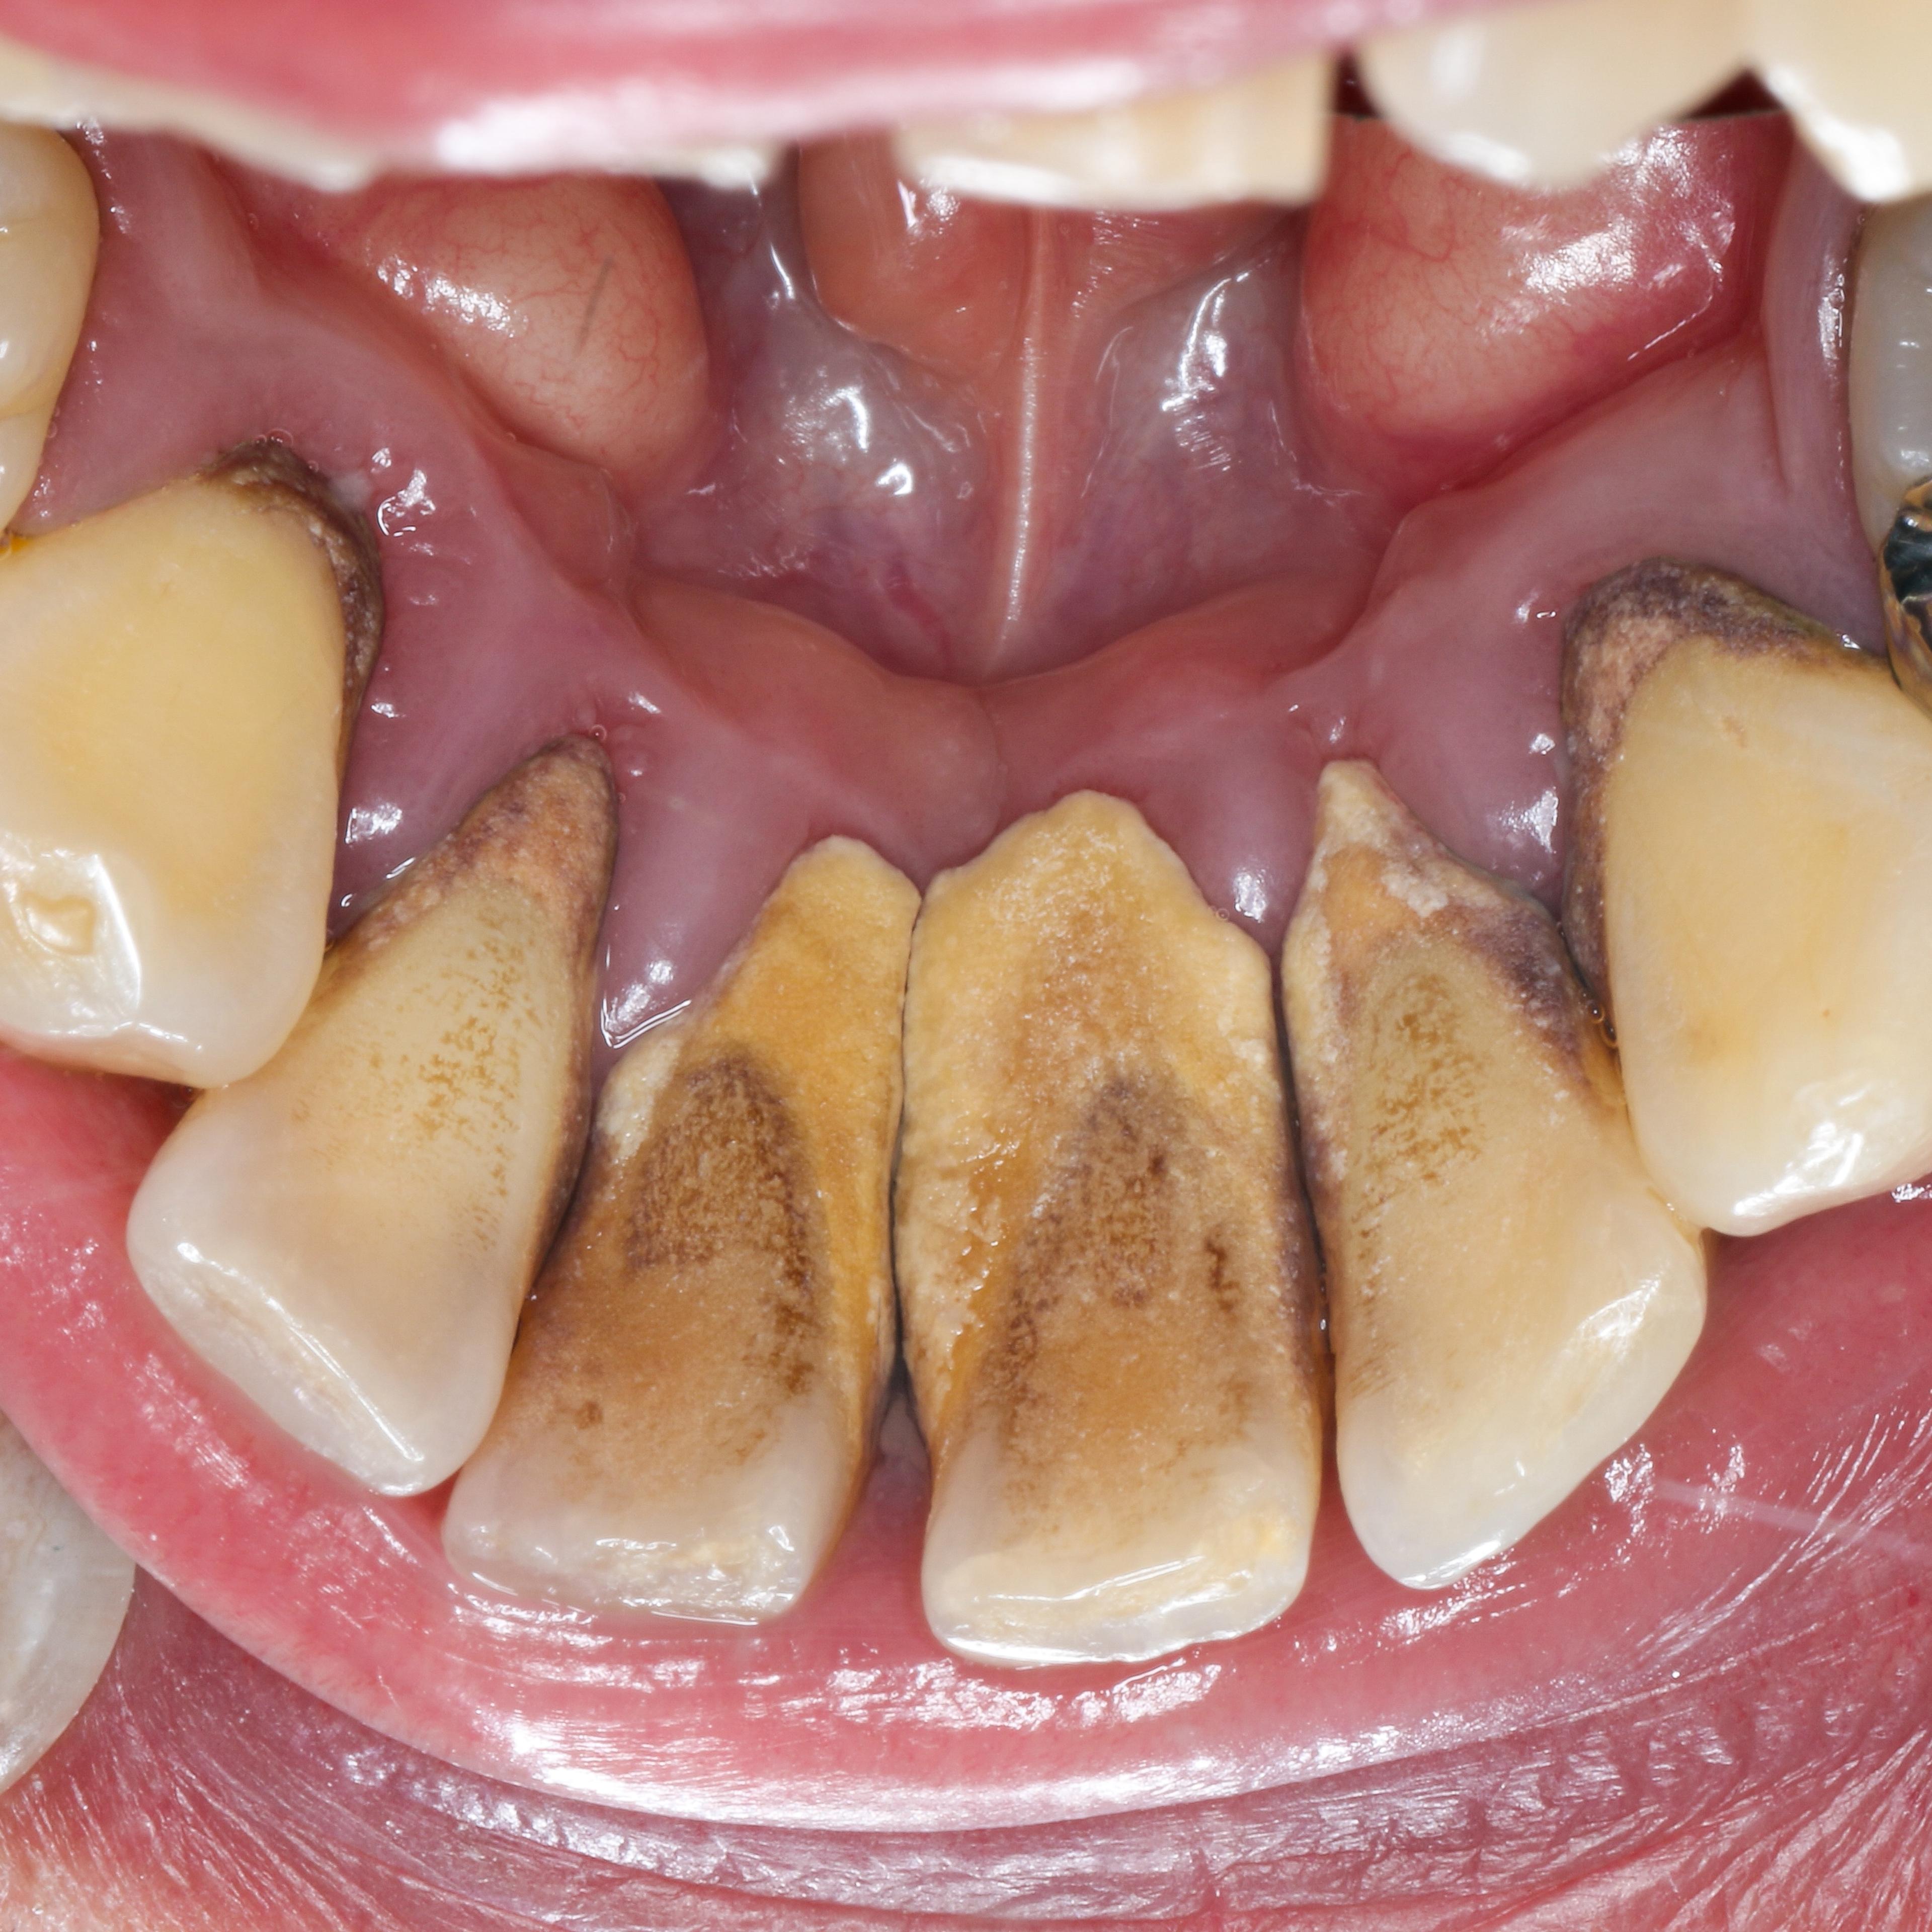

根尖にまで及ぶ透過像

右下1をフォーカスしてみると、根尖に及ぶ透過像がみられます。画像の中央黒い部分になりますが、ここには歯を支える骨はありません。歯周ポケットの深さはもはや測定不可

教科書的には間違いなく抜歯となりますが、ここで諦めるのはまだ早く、回復出来る可能性もあります。原因除去療法により治療を進めることにいたしました。